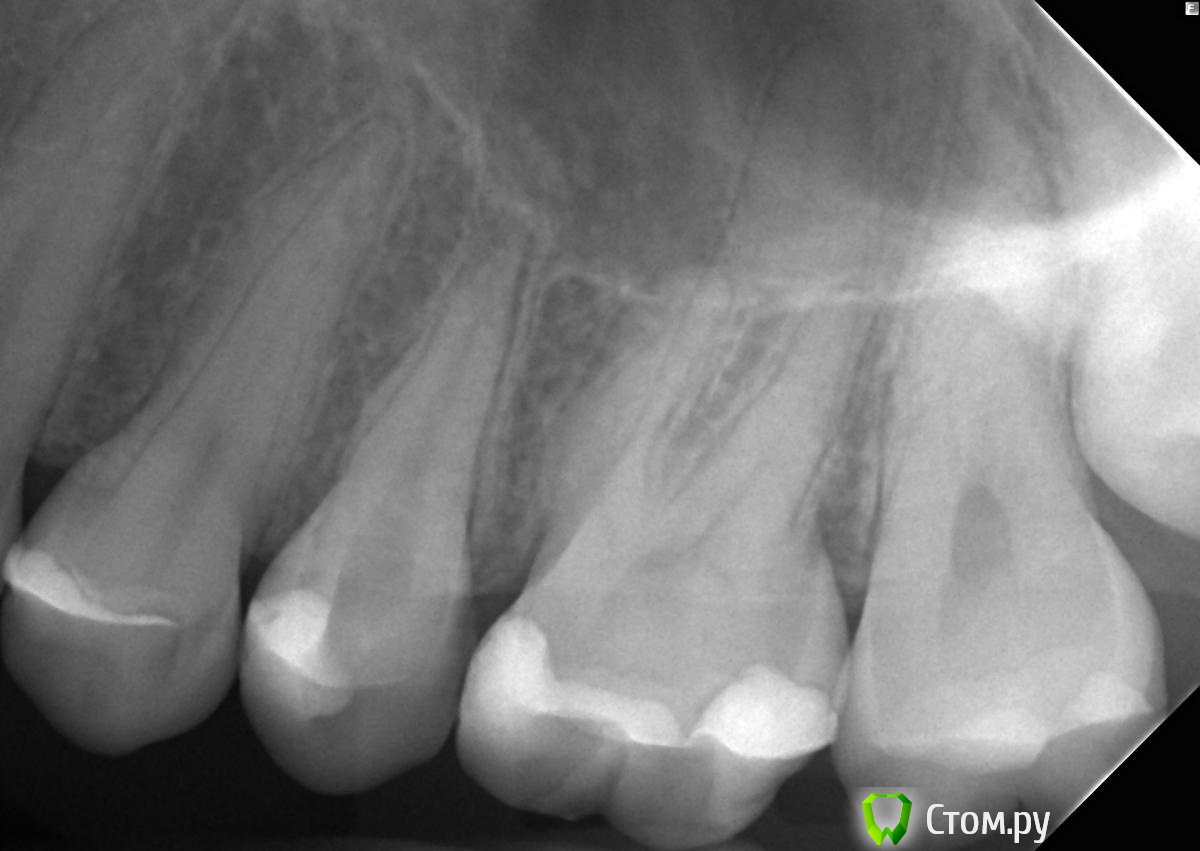

felicidade Опубликовано 18 июня, 2014 Поделиться Опубликовано 18 июня, 2014 Добрый вечер! Сегодня утром мне мой словенский стоматолог запломбировал канал 25-ого зуба. Я, конечно, не стоматолог, но мне кажется, что у меня теперь из корня выглядывают обломок файла и гуттаперча :-( Уважаемые специалисты, скажите, пожалуйста, правильно ли была проведена пломбировка канала? И если нет, то как это можно исправить? Прилагаю снимок зуба до и после пломбировки (17 и 18 июня, соответственно). Спасибо большущее заранее! Ссылка на комментарий

sydnik Опубликовано 18 июня, 2014 Поделиться Опубликовано 18 июня, 2014 Добрый вечер!ничего страшного ,незначительное выведение пломбировочного материла.а сколько каналов доктор запломбировал, не говорил? Ссылка на комментарий

faity Опубликовано 19 июня, 2014 Поделиться Опубликовано 19 июня, 2014 Добрый вечер! ничего страшного ,незначительное выведение пломбировочного материла. а сколько каналов доктор запломбировал, не говорил? верхушки 2 штуки, за обе вышли, ты из-за облачков про канал спросил? felicidade вам нужно сделать снимок в другой проекции, как бы сбоку, и естественно выложить его нам) Ссылка на комментарий

felicidade Опубликовано 19 июня, 2014 Автор Поделиться Опубликовано 19 июня, 2014 Т.е. вероятно, что тут целых 2 корня? Блин :-(Жевать не больно, зуб после депульпации (начало мая) ни на что не реагирует. А можно ли сделать, допустим, CBCT, если рентгеном не получится сделать снимок в другой проекции? У меня сильный рвотный рефлекс, каждый рентген - пытка :-( Ссылка на комментарий

sydnik Опубликовано 19 июня, 2014 Поделиться Опубликовано 19 июня, 2014 (изменено) faity ты из-за облачков про канал спросил?да, насторожили Изменено 19 июня, 2014 пользователем sydnik Ссылка на комментарий

faity Опубликовано 19 июня, 2014 Поделиться Опубликовано 19 июня, 2014 Т.е. вероятно, что тут целых 2 корня? Блин :-(Жевать не больно, зуб после депульпации (начало мая) ни на что не реагирует. А можно ли сделать, допустим, CBCT, если рентгеном не получится сделать снимок в другой проекции? У меня сильный рвотный рефлекс, каждый рентген - пытка :-(корень может быть и один, а верхушки может быть дведелайте прицельник в другой проекции если хотите, для подавления рвотного рефлекса попросите доктора смазать линию А гвоздичным маслом или эвгенолом. Ссылка на комментарий

DokDent Опубликовано 19 июня, 2014 Поделиться Опубликовано 19 июня, 2014 похоже что всё-таки 2 Ссылка на комментарий